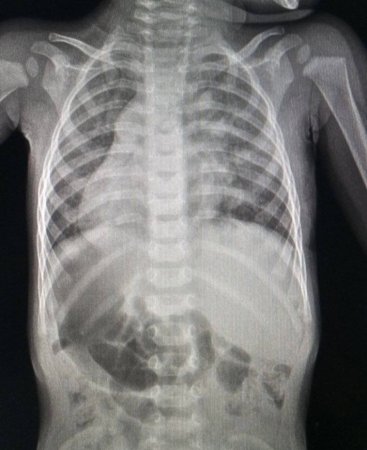

У Львів лікарі здійснили складну та водночас надзвичайно делікатну операцію, врятувавши життя однорічного хлопчика із Закарпаття, який народився з рідкісною анатомічною особливістю — дзеркальним розташуванням внутрішніх органів.

Цей стан, відомий у медицині як Situs inversus, сам по собі трапляється нечасто, однак ситуацію ускладнила ще й серйозна вроджена вада серця. Під час обстеження у віці 9 місяців у дитини виявили дефект міжпередсердної перегородки з аномальним дренажем легеневих вен — патологію, яка вимагала негайного хірургічного втручання.

Кардіохірурги зважилися на малоінвазивну операцію, обравши складний, але щадний метод доступу — через невеликий розріз під пахвою. Під час втручання лікарям вдалося усунути дефект і відновити правильний кровотік, попри нестандартне розташування органів.

Поєднання дзеркального розташування органів і складної серцевої вади створює додаткові виклики для хірургів, адже анатомія пацієнта «змінює правила гри» під час операції. Саме тому подібні втручання вважаються високотехнологічними та потребують великого досвіду медичної команди.